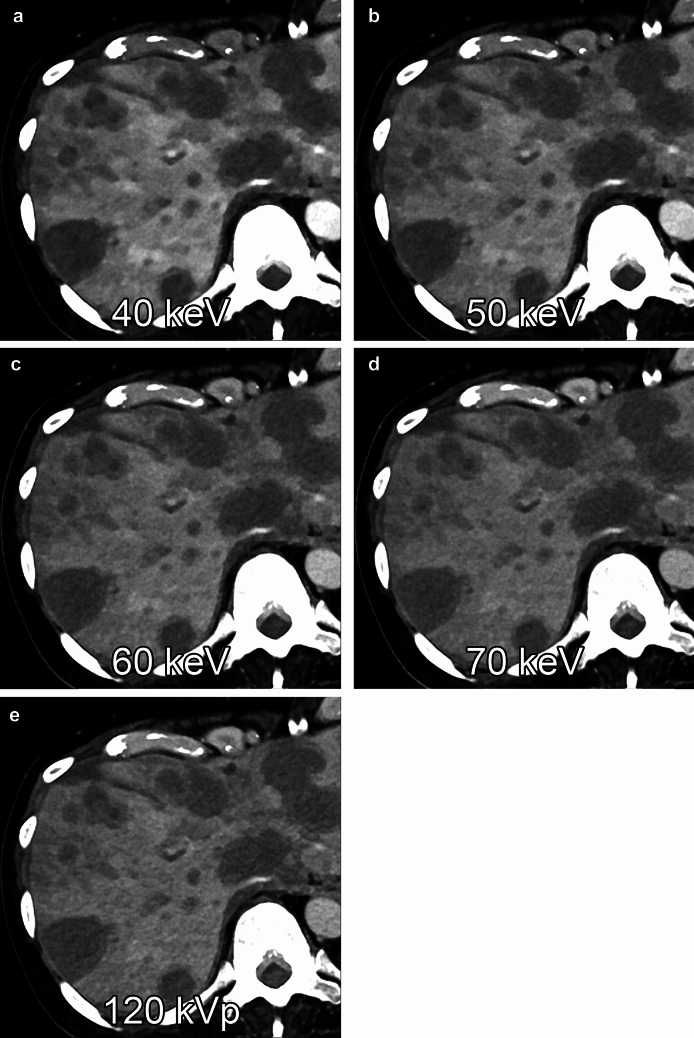

Fig. 6.

Multiple metastatic liver tumors from pancreatic cancer were shown on virtual monochromatic images at 40 (A), 50 (B), 60 (C), and 70 keV (D) and polychromatic image (i.e., T3D) acquired with photon-counting CT at 120 kVp (E) during the portal venous dominant phase. The contrast-to-noise ratios between the liver metastasis and the liver parenchyma are 14.6, 11.9, 9.8, 8.5, and 7.4, respectively

Liver metastasis is the most common type of liver cancer, and most cases have hypovascular characteristics. Virtual monochromatic images with photon-counting CT show reduced image noise compared to conventional single-energy CT and improved conspicuity of hypovascular liver metastases at lower keV levels, and patients with a high body mass index benefit especially from photon-counting CT compared to conventional CT [26] (Fig. 6).